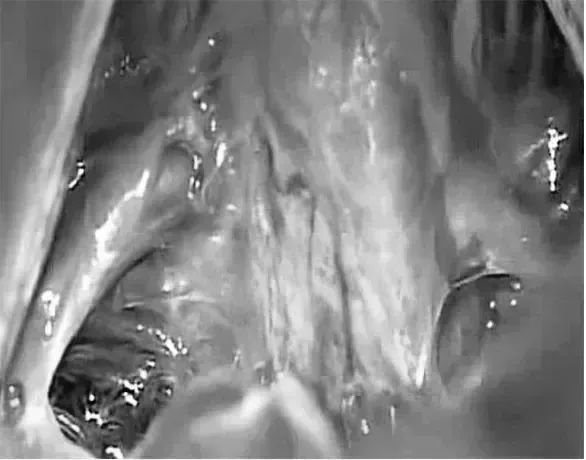

术中照片显示Galenic静脉引流通过小脑上蚓,小脑左侧旁入路暴露的路线